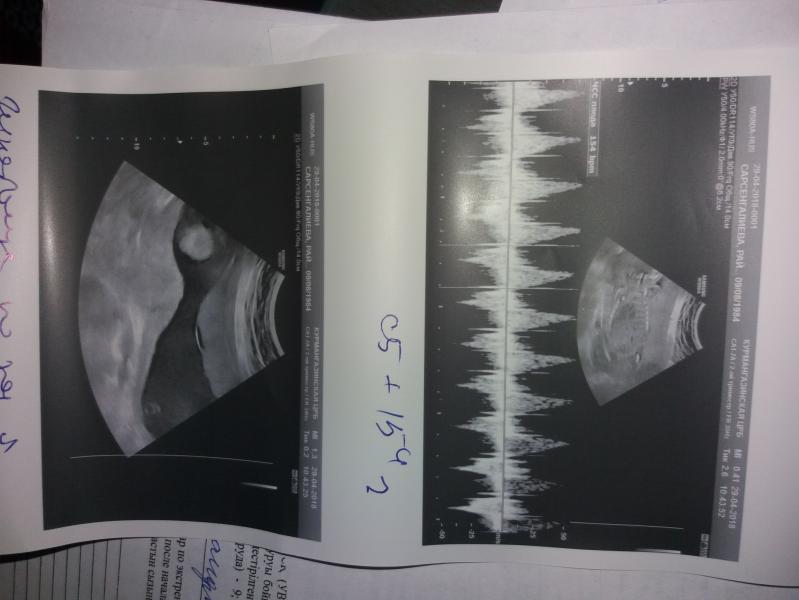

Угроза прерывания изо тонуса по задней стенке матки,беременность 22-23 недели.на момент осмотра правый коленный сустав в развернутом виде,иследовать не удается.рекомендовано дообследование узи плода дабы исключить костно-суставную патологию конечностей плода справа

Упб- угроза прерывания беременности . Беременность 22-23нед. Рек-но узи плода исключить костно-суб....что-то там